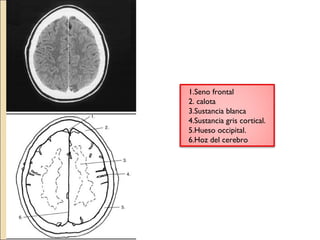

1.Seno frontal

2. calota

3.Sustancia blanca

4.Sustancia gris cortical.

5.Hueso occipital.

6.Hoz del cerebro

1.calota

2.Hueso del cráneo.

3.Seno frontal

4.Hoz del cerebro

5.Espacio subaracnoideo.

6.Densidad de la sustancia gris

7.Sustancia blanca.

8.Lobulo frontal.